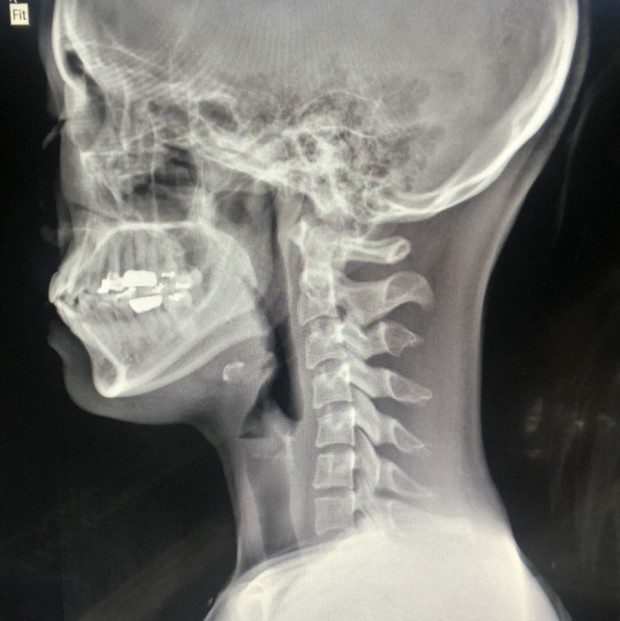

목디스크(경추 추간판 탈출증)는 경추(목뼈) 사이의 디스크가 탈출하거나 변형되어 신경을 압박하는 질환입니다. 이로 인해 다양한 증상이 나타날 수 있으며, 아래에 10가지를 아주 자세히 설명드립니다.